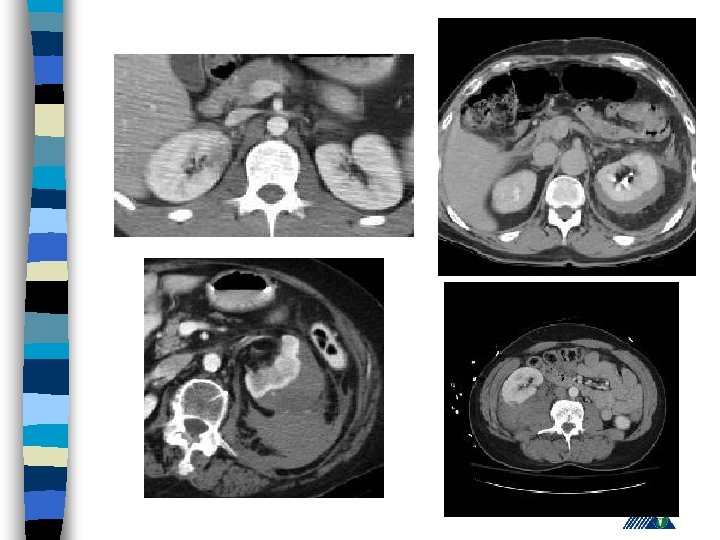

Renal Trauma n Blunt : (85 -90% ) – vehicle accident, fall, rapid deceleration, iatrogenic n Penetrating : Gunshot and (85 -90 % associated with intraabdominal or thoracic injury)

Renal Trauma - Diagnosis History n PE (lumbar echimosis, pain with palpation) n Hematuria n – (Renal vascular injury - 36 % not associated with hematuria) n Variable clinical presentation (asymptomaticshock)

Radiologic Imaging n n n KUB (loss of psoas or renal contour) IVU (delayed renal function, nonhomogenous collecting system) USG (lumbar hematoma and urinoma lokalizasyonu) Computerized Tomography Renal angiography

American Association for the Surgery of Trauma Organ Injury Severity Scale for the Kidney Grade Tip Tanım 1 kontüzyon Mikroskobik ya da gross hematuri, ürolojik incelemeler normal hematom Sub. Kapsuler, genişlemeyen parankimal hasar yok hematom Genişlemeyen perirenal hematom , renal retroperitona sınırlı laserasyon <1 -cm derinlikte parenkimal korteks hasarı, üriner ekstravazasyon yok 3 laserasyon >1 -cm derinlikte parenkimal korteks hasarı, üriner ekstravazasyon yok 4 laserasyon Medulla ve toplayıcı sisteme ulaşan parenkim hasarı vasküler Renal arter ve vende hemoraji içeren hasar laserasyon Tamamen parçalanmış Böbrek vasküler Renal hilusun ayrılması 2 5

Expectant Management: n Hemodynamically stable, well defined and non-expanding injury on CT scan n 88 % patienst are observed n If there is associated gross hematuria, admit and observe

Surgery : Absolute Indication – Persistant renal bleeding – Expanding perirenal hematoma – Perirenal hematoma with pulsation n Relative indication – Urinary extravasation – Inability in proper staging – Delayed arterial injury – Canlı olmayan doku varlığı n